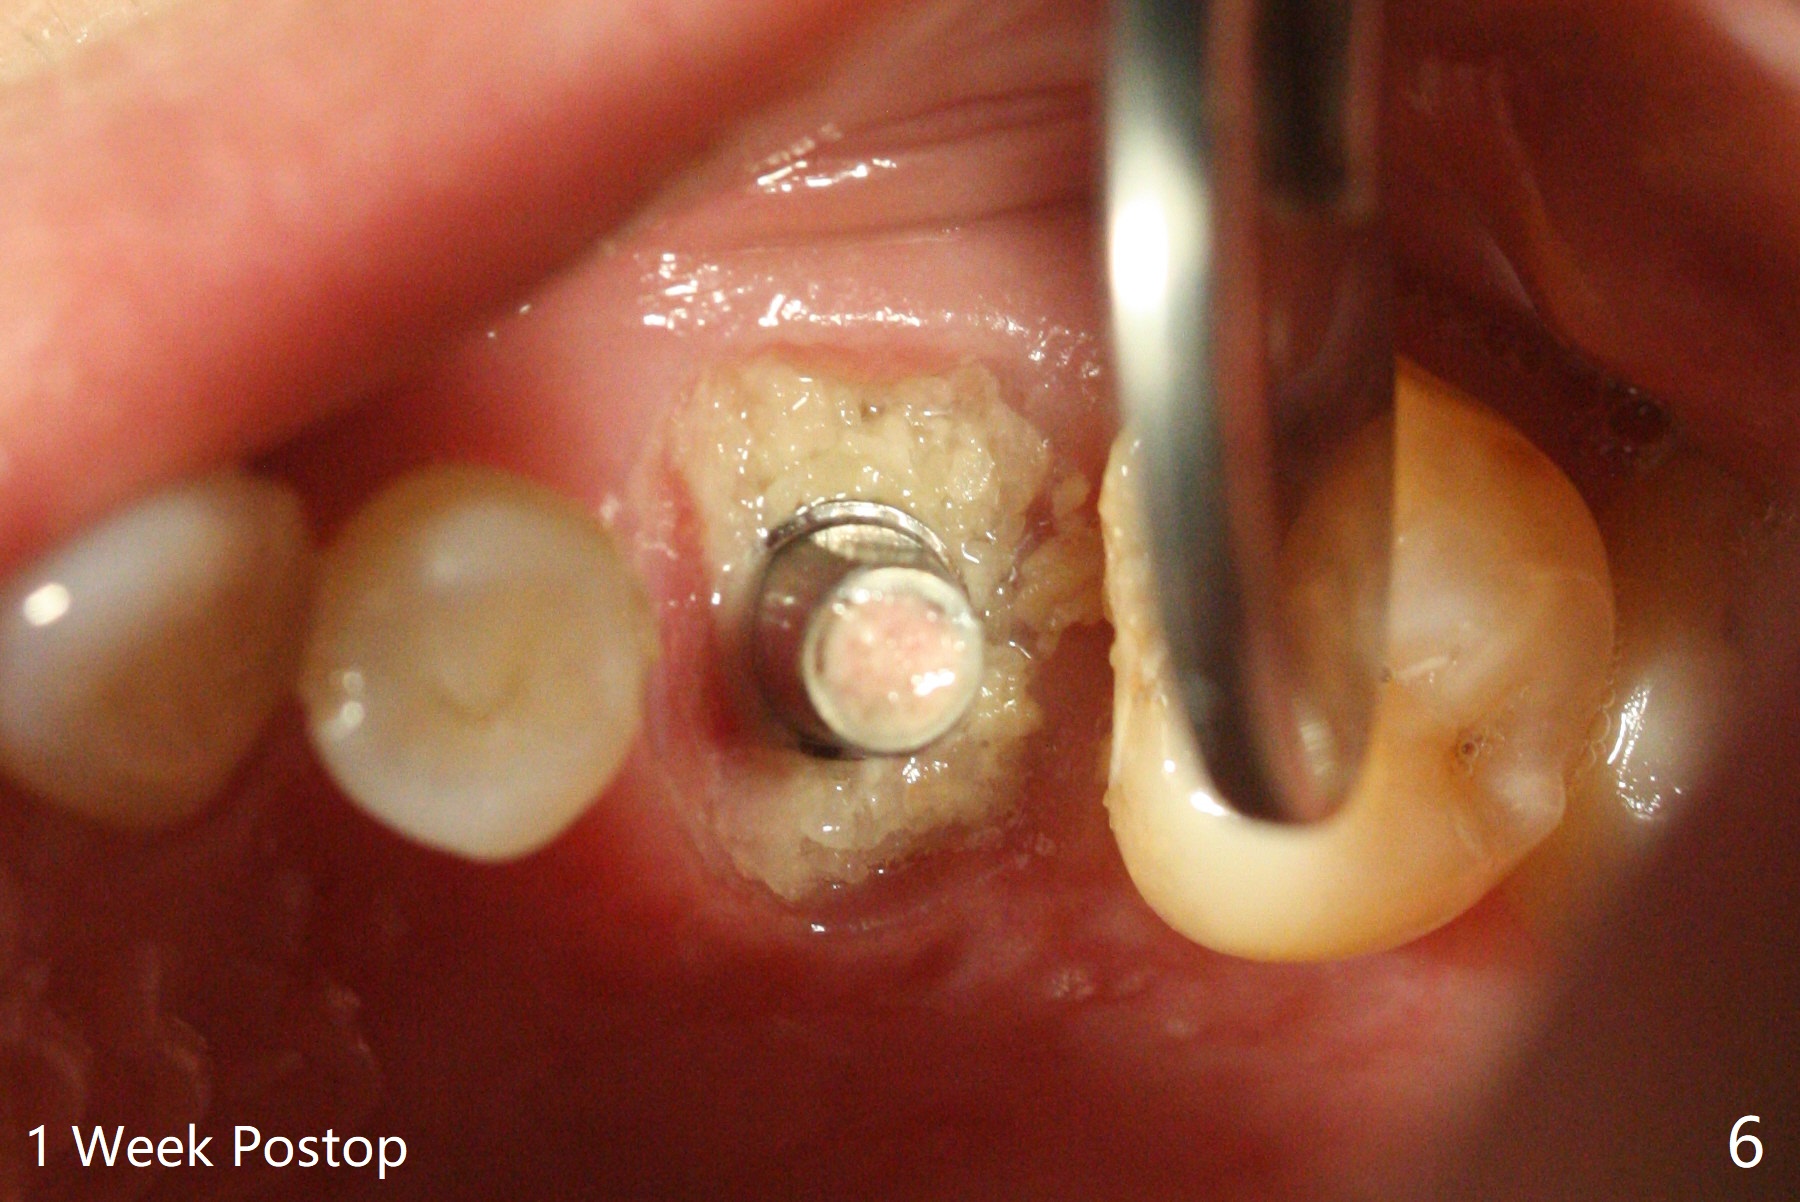

虽然没有保留左上6牙根,但是导板好像帮助钻洞(O)正好位于中隔当中(图一,二)。使用4.5(不是4.0)x10毫米钻头后,粘性骨粉和报废植体完成上颌窦提升术(图三:S)。拔除第一磨牙后发现第二磨牙近中面龋齿,立刻进行保守修补(图三:箭头);两个磨牙之间还有骨质吸收(*)。放置正式植体(10Ncm)后(图四),三个牙槽窝填入骨粉,包括近中颊侧(MB)和远中颊侧(DB),这时磨牙间缺损初步填补(*),然后放置基台以及基台周围骨粉,进一步充填磨牙间缺失(图五:*)。术后临时牙冠脱落两次,病人自己放回去,术后一周取出牙冠,骨粉还在(图六),腭侧有单纯疱疹病变(图七:>),开抗病毒漱口水处方,然后使用临时粘固粉。术后7个月15号牙近中牙槽嵴增高大约1.4毫米(图八:空箭头,从近中最颈部树脂算起)。术后七个月临时牙冠一直使用,防止食物坎塞,有利于骨质再生。术后7个月基台在口内没有更动(术中手拧紧),牙冠口内粘固,少量粘固剂遗留(图八:^)。牙冠/基台取出,去除粘固剂,牙冠/基台就位,用扳手拧紧(30 Ncm),基台与植体仍保持完全接触(图九)。只要植体植入角度好,没有倒凹,牙冠/基台再次就位就没有问题。